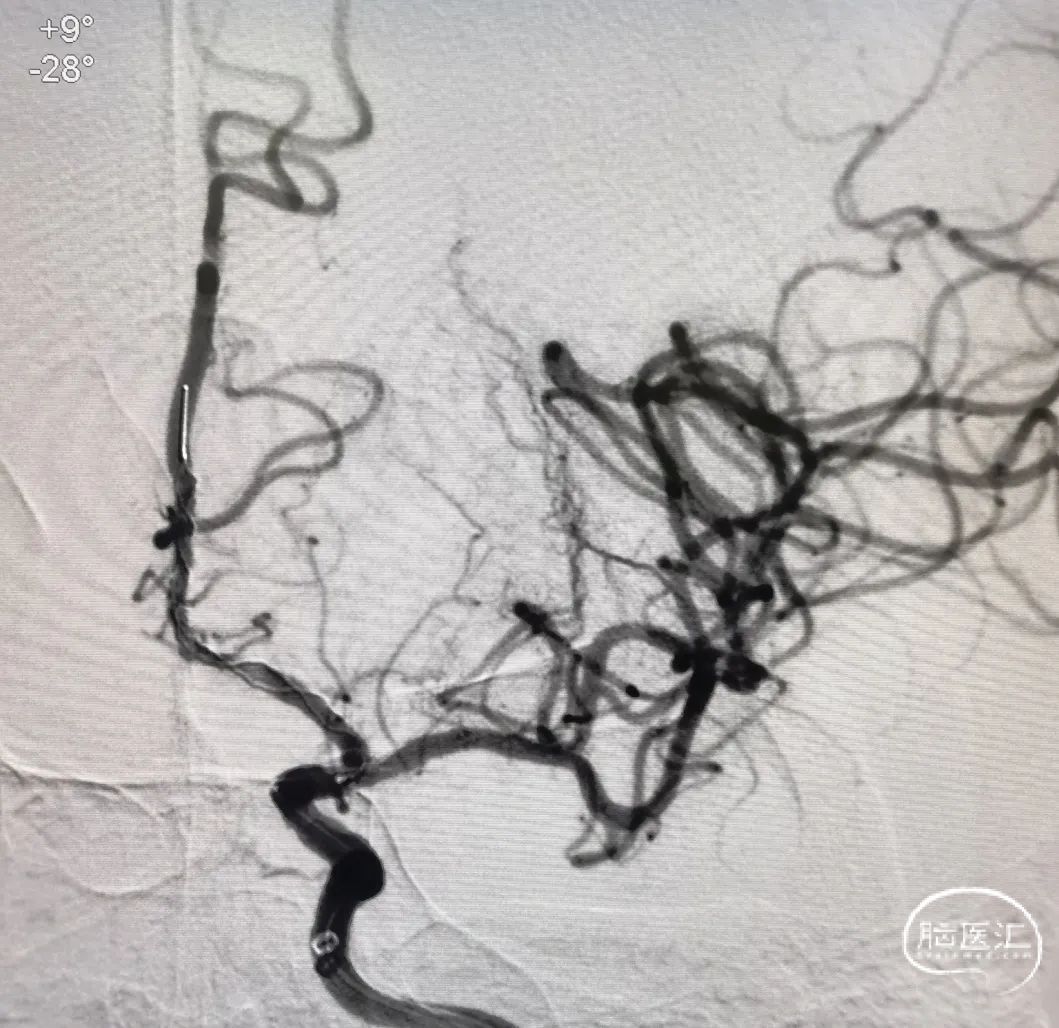

右侧颈总正侧位:见右侧颈内动脉闭塞,颅外血管代偿良好。

左椎正侧位:椎基底动脉未见异常,可见部分代偿。

左颈总正侧位:左侧颈内动脉闭塞,可见血管残端。

术后正侧位造影:全程血流恢复满意。